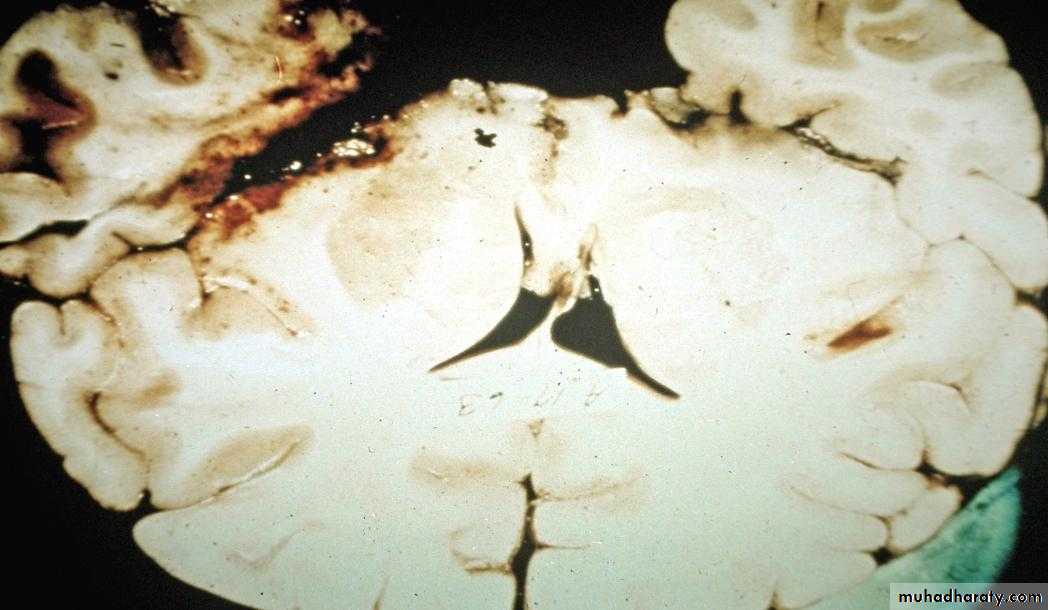

Herpes Encephalitis

Accounts for 10-20% of viral encephalitis2.3 cases per 1 million

Temporal lobe involved

Diagnosis: LP: Increased CSF protein, leucocytes with lymphocytic predominance and increased CSF RBCs due to hemorrhagic necrosis

Treatment: IV Acyclovir, reduces mortality. Despite treatment mortality upto 15% with survivors with longterm cognitive impairments